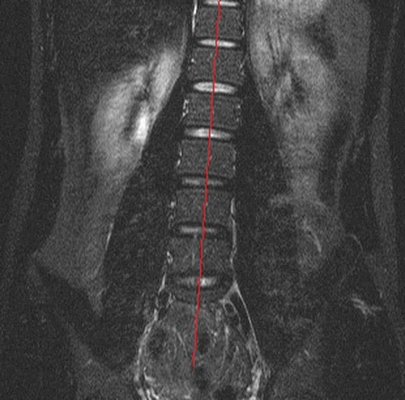

Оценка степени бокового искривления при МР-сканировании (красной линией указана ось позвоночного столба)

Результаты МР-сканирования — это множественные снимки исследуемой области в различных плоскостях. По изображениям обнаруживают искривление. При наличии программного обеспечения, которое преобразует данные в трехмерную картину, специалист может точно установить диагноз и оценить степень деформации. Поэтому на вопрос: «Показывает ли МРТ сколиоз позвоночника?» - врачи дают утвердительный ответ. Но МР-сканирование — это дорогостоящая процедура. Потому в качестве основного метода диагностики сколиоза МРТ не применяют.

На обычном рентгеновском снимке врач сразу же видит искривление позвоночника в сагиттальной или коронарной плоскости. Четкие контуры структур на изображении позволяют быстро установить тип деформации. Специальные методики подсчета применяют для определения степени отклонения позвоночника от центральной оси. Рентгенография позволяет отличить структурный тип сколиотических изменений от неструктурного. Первый вариант возникает на фоне патологических процессов непосредственно в позвоночнике, а второй — из-за повышенного тонуса мускулатуры спины или травмирования нервных образований, например, грыжей диска. Таким образом, магнитно-резонансная томография может быть использована только как вспомогательный способ диагностики собственно сколиоза.